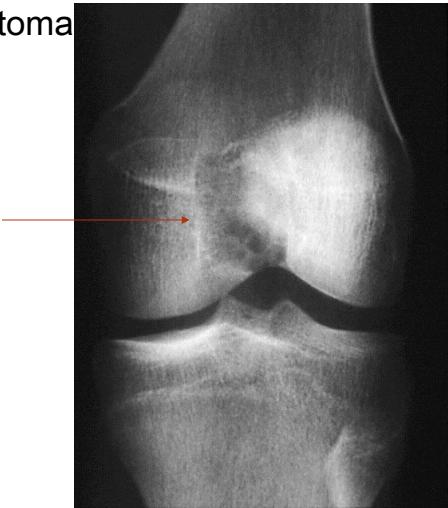

Giant Cell Tumor

Aneurysmal Bone Cyst

/// gce an?

site: distal femur size: Most (involving how much? / cm?) matrix: mixed - mainly radiopaque , wide zone of transition, cortical destruction, resulted periosteal reaction, and codman’s triangle soft tissue involvement: